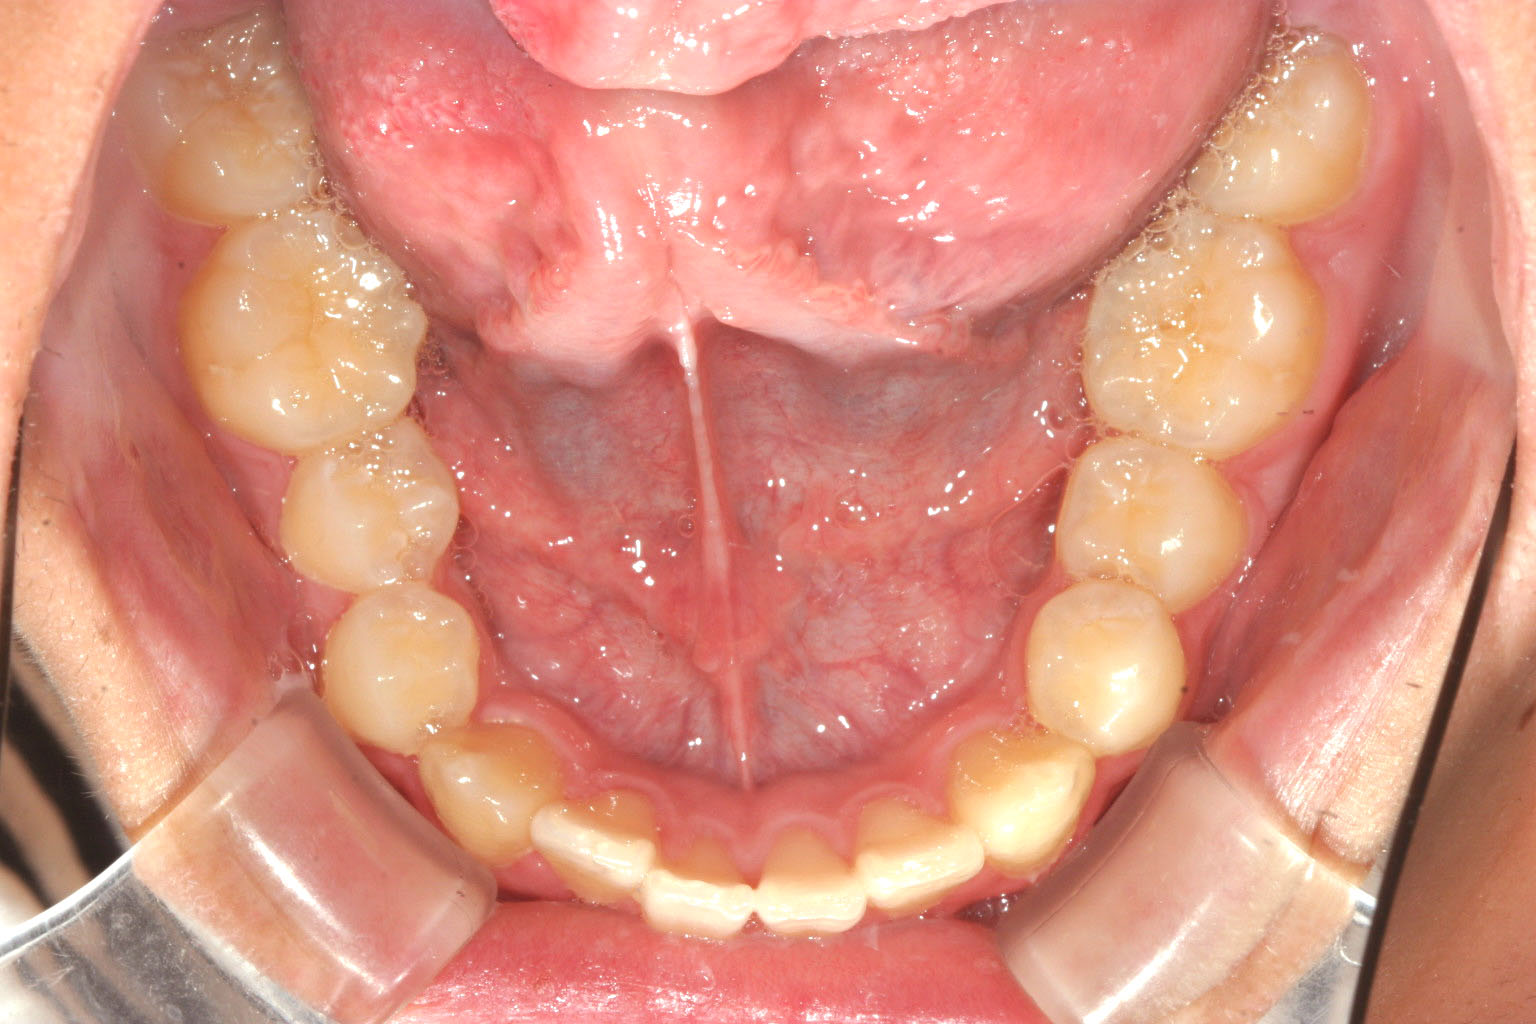

歯列に問題は無さそうです。

綺麗に並びました。

少しアーチが広がりました。